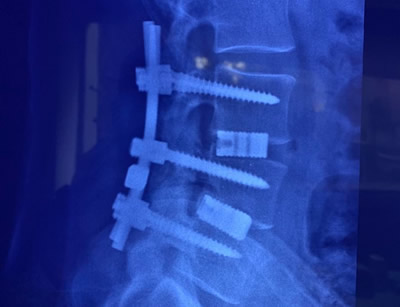

GALLERY

Images gallery